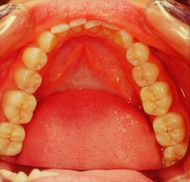

The finalization of the definitively diagnosed clinical case of DTMs resulted in a restoration of the masticatory function, disappearance of the symptoms as well as an aesthetic improvement. The various phases of the rehabilitation can be followed in the gallery of images in figure 9. In particular, the Functional Neuro-Evoked Centric position is not only centered having moved slightly to the right but also retruded. It is interesting to make a comparison with figure 5a to understand the spatial differences. Element 22, in fact, is no longer in crossbite but in a head-to-head position while element 23 has a much more incisal centric contact with respect to the previous clinical situation, so as to note the occlusal space in the medial area of element 24 which it was generated with the current mandibular spatial position determined with the Functional Neuro Evoked Centric. This new occlusal arrangement was only possible because the stable and mainly frozen centric position in the molar sector. The molars through the previously exposed neuromotor balance on the centric cusp stabilize the occlusion and generate a bilateral balance in the mandibular movements as will be shortly described.

In figure 9c and 9d, we can see not only the well balanced centric contacts but above all the mediotrusive excursions. A few more words should be spent on this subject. Benedikt Sagl et al.[19] state, in their study in which the contribution of tooth inclination, medio-otrusive and laterotrusive excursion and von Mises stresses on the articular disc was analysed, that mediotrusive bruxing generates higher loads than laterotrusive simulations. In this sense it is not clear whether the mediotrusive contacts are a protective or a pejorative element in the generation of temporomandibular joint disorders. So much so that an article by Walton TR and Layton DM[20] increases the confusion as they first state that the presence of TM interference in patient populations is large and varies from 0% to 77% and then conclude that TM interference should be avoided in any occlusal treatment regimen to minimize pulpal, periodontal, structural and mechanical complications or exacerbation of temporomandibular disorders (TMD). The confusion increases when he concludes that natural molar MT interferences should only be eliminated if signs and symptoms of TMD are present. The question that arises is the following

In figure 9c and 9d the mediotrusive path highlighted with the articulation paper was constructed by calculating the angle determined by the unilateral Root-MEPs which displaces the mandible by about 1/2mm on each side. By programming the Denar joint (figure 10) it was possible to construct an excursion with different angles between the TMJ, molar and canine. This procedure generates a natural path in which the canine guides together with the mediotrusion to protect the TMJ from the masticatory load that exists beyond bruxism.